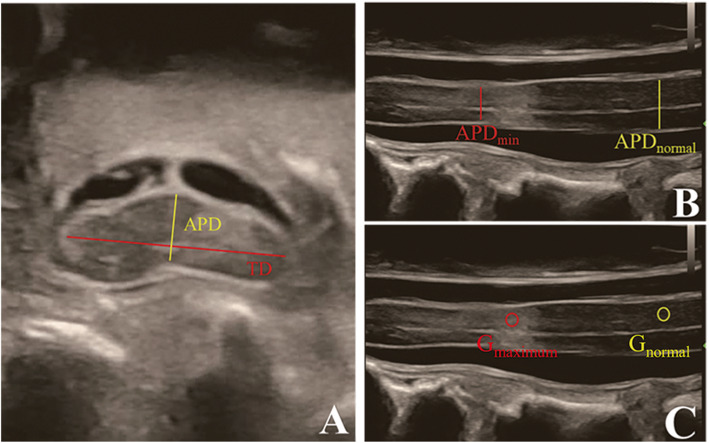

On IOUSI, the midsagittal APD (the midsagittal slice was determined by the visualization of the central canal of spinal cord) at the narrowest level (APDmin) and the compression-free level (APDnormal) were measured and then calculated the MSCC (MSCC = APDmin/APDnormal). The APDtraverse and the TD of the narrowest traverse slices were measured and then calculated the CR (CR = APDtraverse/TD).

In order to avoid the deviations caused by variations between machines and operators, we defined the gray value ratio, Rgray, by calculating the ratio of the gray value in the midsagittal IOUSI at the narrowest level to that at the lesion-free level: Rgray = Graynarrowest/Graynormal.

The IOUSI Rgary and was measured according to the methods described in previous studies about the measurement of signal change rate on T2W MRI with few modifications [7, 21]. In brief, for patients with macroscopic hyperechogenicity on IOUSI, a circle of 0.1 cm2 was drawn with the maximum brightness point as the center, and a circle of 0.1 cm2 was drawn on the lesion-free level, then the gray values of both circles were measured by ImageJ respectively, and calculated the Rgray. For patients without different visible brightness within the spinal cord, a circle of 0.1 cm2 was drawn within the maximum compression level, and another circle of 0.1 cm2 was drawn on the lesion-free level, then measured the gray values and calculated the Rgray. All circles avoided involving the central canal of spinal cord. (Fig. 2).

Fig. 2.

a Traverse images at the maximum level of patient with degenerative cervical myelopathy (DCM), depicting the measurements required to calculate the compression ratio (CR). Measurements for CR of intraoperative ultrasound imaging (IOUSI), including the anteroposterior diameter (APD) and the traverse diameter (TD) of the spinal cord. b) Midsagittal IOUSI of patient with DCM, depicting the measurements required to calculate maximum spinal cord compression (MSCC). Measurements for MSCC of intraoperative ultrasound imaging (IOUSI), including the width of the spinal cord at the narrowest site (APDmin) and the width of the spinal cord at the normal site (APDnormal). c Midsagittal IOUSI of patient with DCM, depicting the measurements required to calculate the gray value ratio (Rgray). A midsagittal intraoperative ultrasound imaging (IOUSI) of a patient, the measurements required to calculate the gray value ratio (Rgray), including a 0.1 cm2 measurement of the gray value at the site of the maximum compression level of the spinal cord (Gmaximum) and 0.1 cm2 gray value measurements at the lesion-free site (Gnormal)